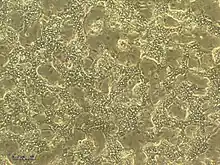

HepaRG cells are bipotent progenitors, capable of differentiating into both biliary and hepatocyte lineages. In culture, they are organized in well-delineated trabeculae with many bright canaliculi-like structures under 2D and 3D configurations. They are polarized cells that breathe aerobically, consume lactate, and contain as many mitochondria as the human hepatocytes. The cell line has the potential to express major properties of stem cells including high plasticity & transdifferentiation capacity.